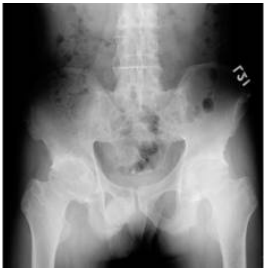

75 一位 37 歲男性病人下背疼痛多年,其骨盆腔 X 光片如圖,最有可能的診斷為:

(A)rheumatoid arthritis (B)osteoarthritis (C)gouty arthritis (D)ankylosing spondylitis